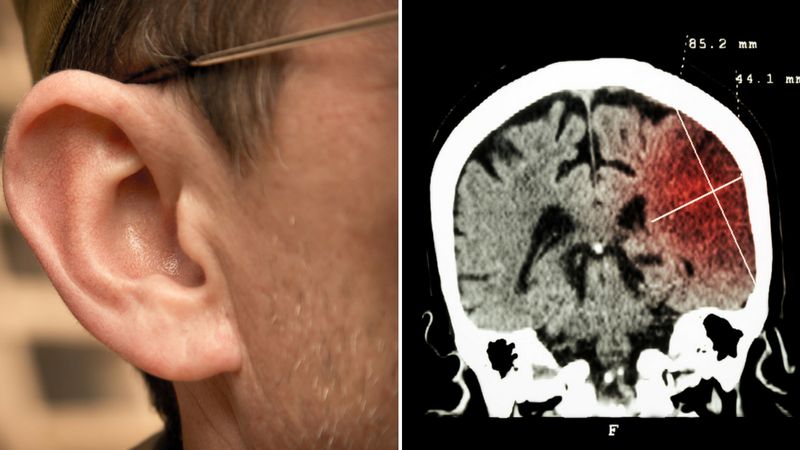

Jeśli myślisz, że to żart – mylisz się! Naukowcy z Izraela odkryli, że kształt ucha może być znakiem tego, że dana osoba narażona jest na wystąpienie u niej udaru. Wskazówką ma być pionowe zagniecenie małżowiny usznej znane jako znak Franka.

Naukowcy przebadali 241 osób, które doświadczyły udaru. Aż u 3/4 spośród nich zauważyli poprzeczną bruzdę na małżowinie usznej. Myślisz, że to nieprawdopodobne, aby ucho pokazywało stan zdrowia? Już tłumaczymy. Według naukowców główną przyczyną udaru jest zatkanie tętnic.

Przytkane naczynia krwionośne sprawiają, że do poszczególnych części twarzy (w tym do uszu) dostaje się mniej krwi, przez co tracą swoją elastyczność. To właśnie brak odpowiedniego ukrwienia ma prowadzić do powstawania bruzdy. Według izraelskich badaczy kształt ucha powinien zostać dodany do listy potencjalnych czynników rozwoju udaru.

Badania przeprowadzone w innych krajach zdają się potwierdzać tę tezę. Te opublikowane w "American Journal of Medicine" potwierdzają, że u 78 spośród 88 przebadanych osób, które przeszły udar, dało się zauważyć charakterystyczne zagniecenie. Czym jednak jest owy znak Franka?

Jego nazwa pochodzi od amerykańskiego lekarza Sandersa T. Franka, który u młodych pacjentów cierpiących na dusznicę bolesną odkrył zmarszczkę na płacie ucha. Znak Franka można zaobserwować u wielu znanych osób, m.in. u Stevena Spielberga czy Mela Gibsona.